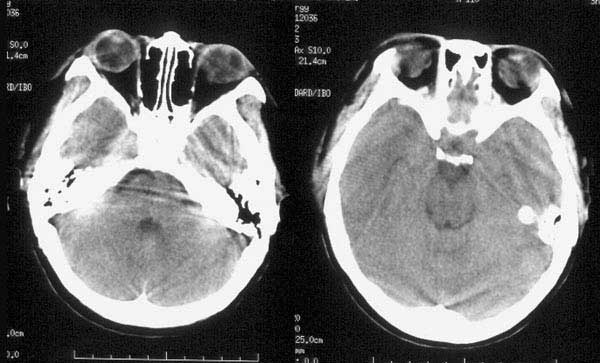

ct平扫:左颞骨内板下见细线形高密度出血影,左侧侧脑室受压变窄,中线结构向右侧移位。大脑镰、小脑幕及左枕部脑沟密度增高。鞍上池、环池均显示不清。

ct诊断:1、左颞硬膜下血肿。

2、蛛网膜下腔出血。

3、脑肿胀。